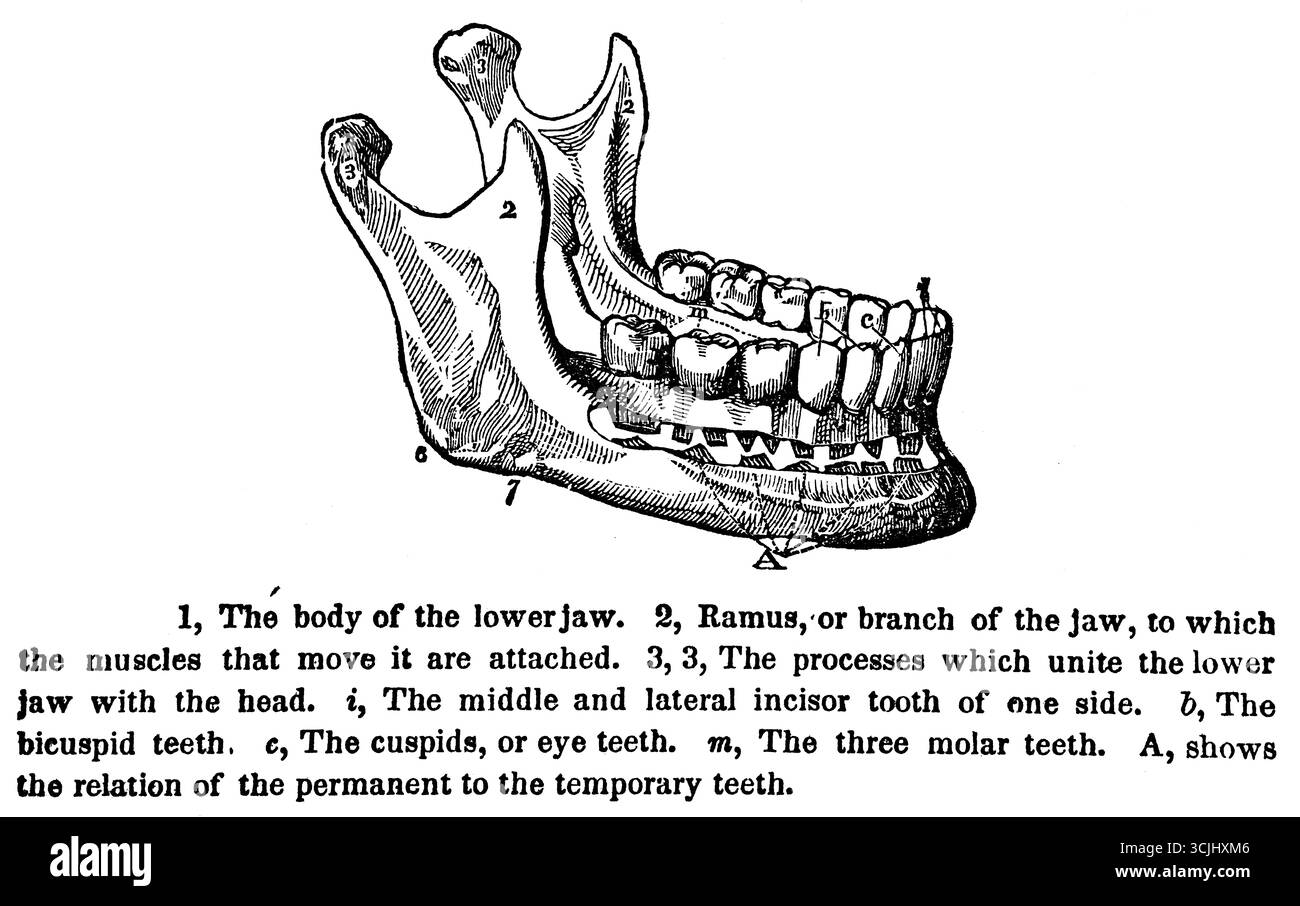

Anatomie des dents, corps de la mâchoire inférieure, illustration historique 1858 Banque D'Imageshttps://www.alamyimages.fr/image-license-details/?v=1https://www.alamyimages.fr/anatomie-des-dents-corps-de-la-machoire-inferieure-illustration-historique-1858-image699872662.html

Anatomie des dents, corps de la mâchoire inférieure, illustration historique 1858 Banque D'Imageshttps://www.alamyimages.fr/image-license-details/?v=1https://www.alamyimages.fr/anatomie-des-dents-corps-de-la-machoire-inferieure-illustration-historique-1858-image699872662.htmlRM3CJHXM6–Anatomie des dents, corps de la mâchoire inférieure, illustration historique 1858